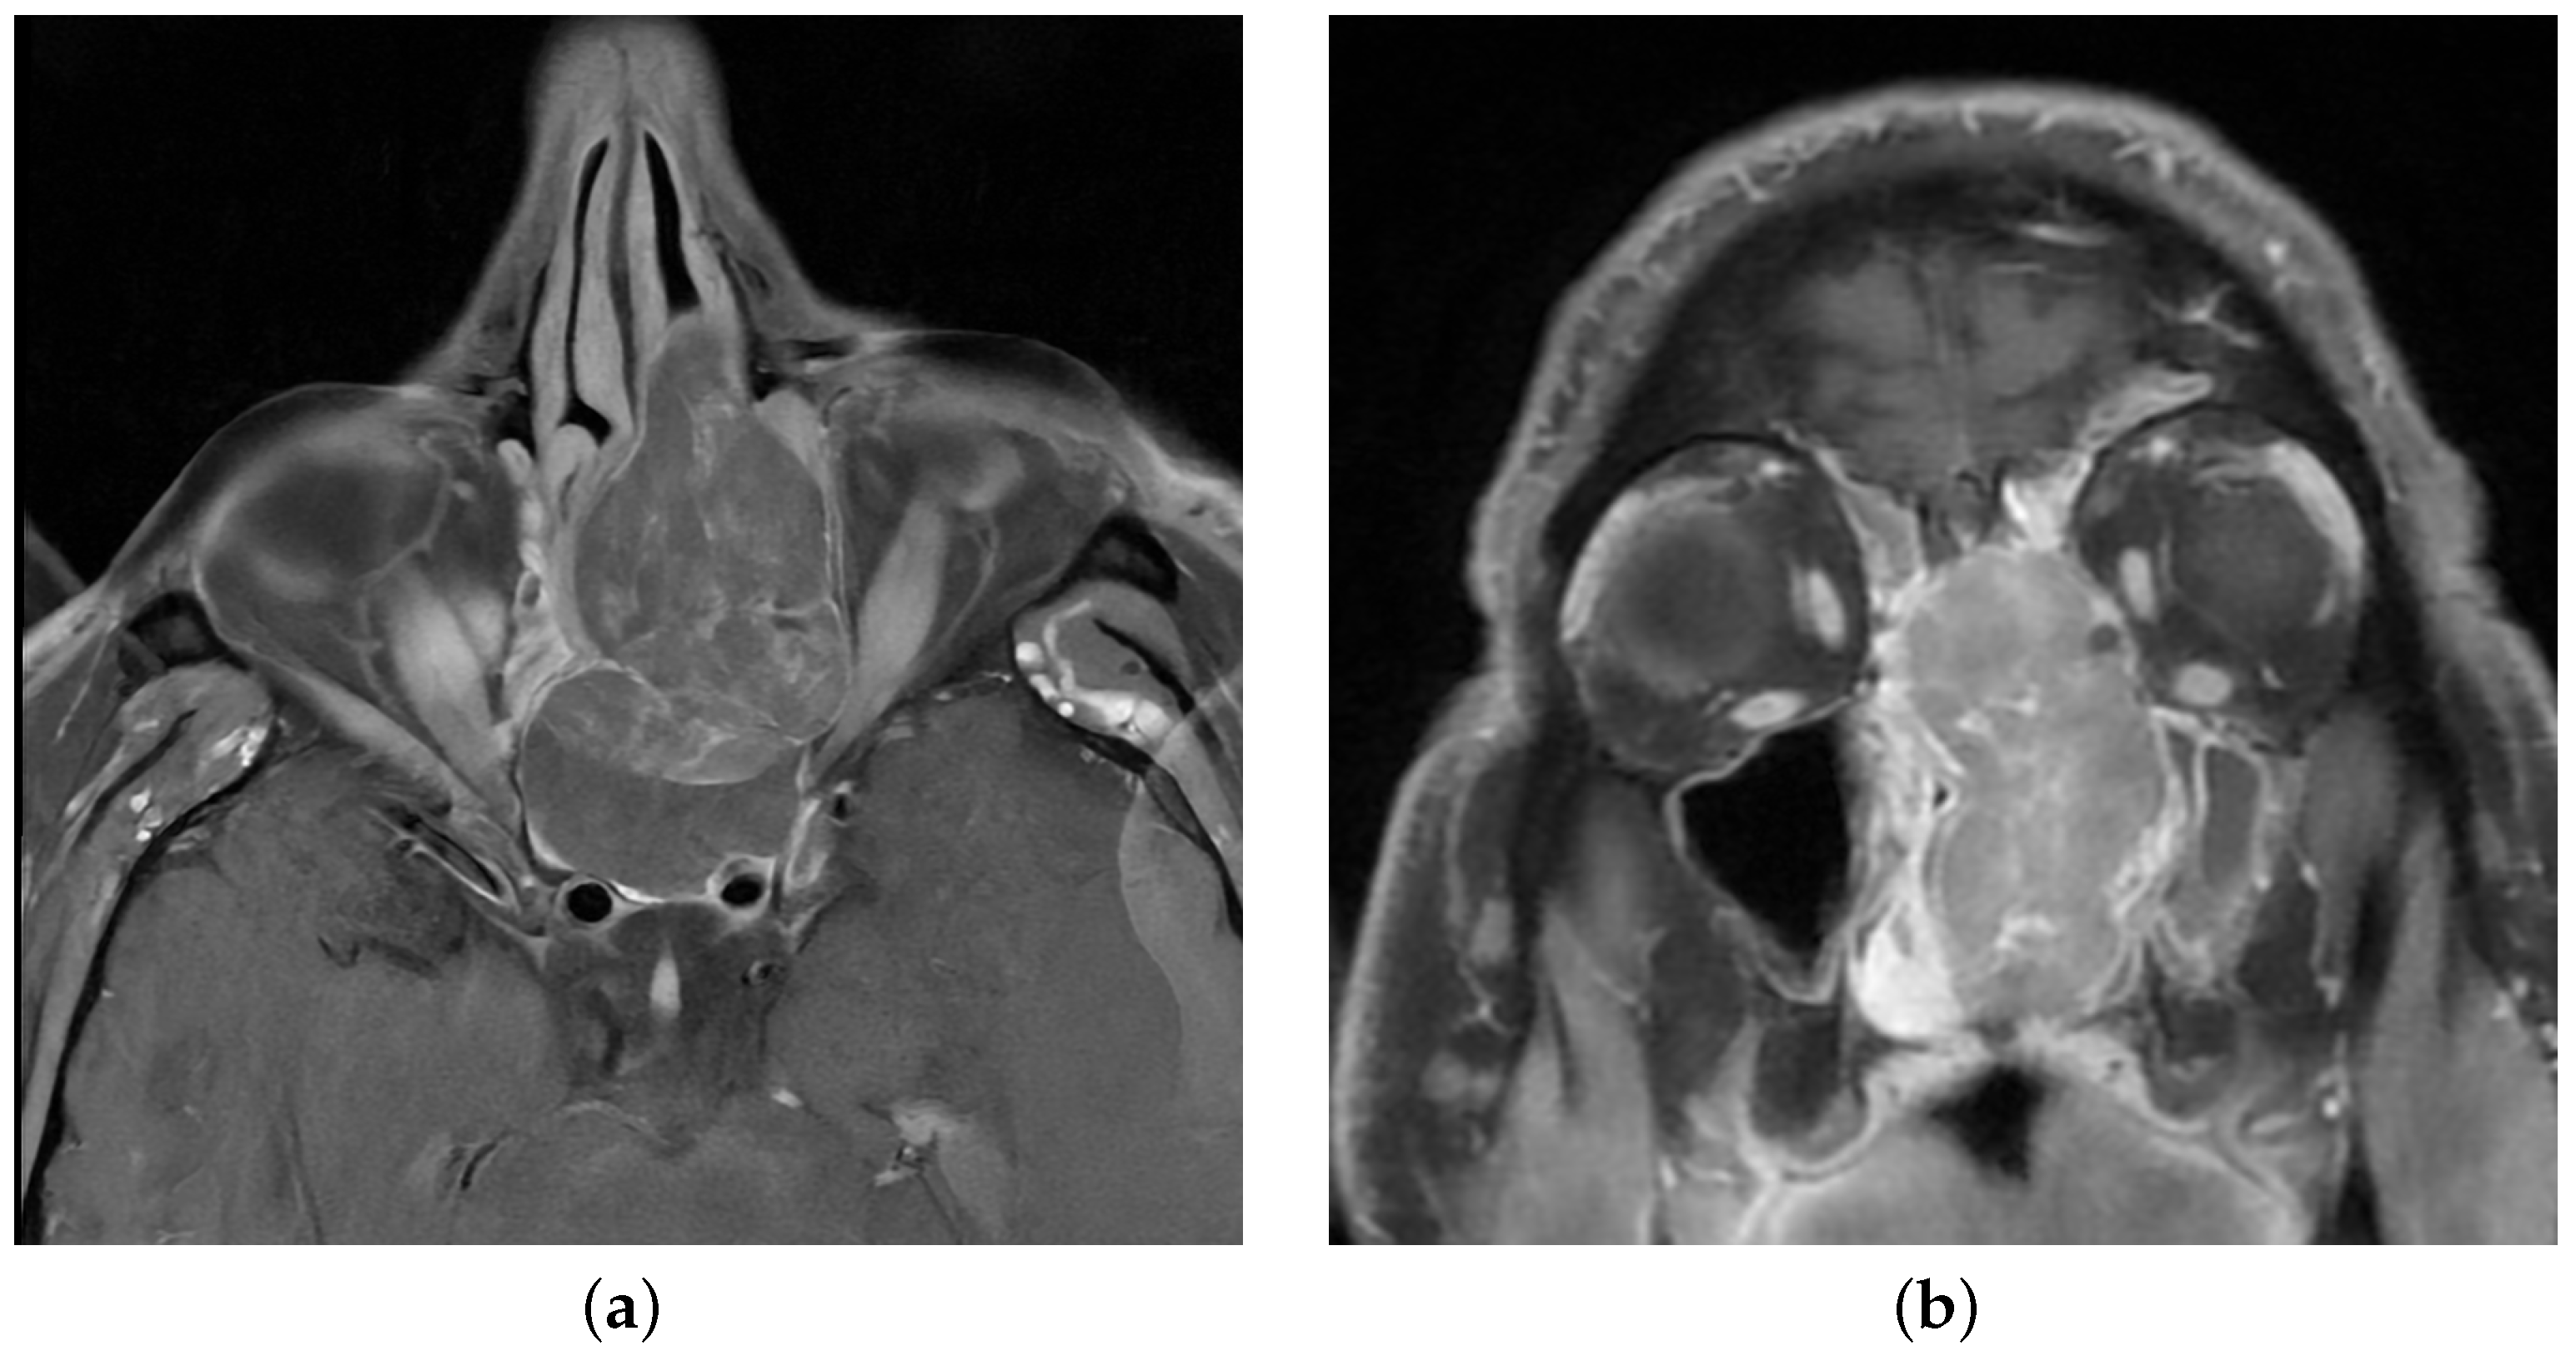

A 48-year-old non-smoker male patient presented with nasal obstruction for over a year. A computed tomography (CT) scan and magnetic resonance imaging (MRI) revealed a large, infiltrating mass involving the left nasal cavity (Figure 1) and ethmoid sinus, extending into the periorbital fat and brain parenchyma at the level of the right gyrus. Biopsy and histopathologic examination led to the diagnosis of SNUC (Figure 2a) with increased H3K27 trimethylation (Figure 2b), compatible with the hypermethylated phenotype. It was classified as stage cT4b based on the radiological findings. Molecular profiling on the biopsy sample showed a previously not reported mutation of IDH2 (R172A) and a common TP53 mutation (R273H) [8,9]. A positron emission tomography (PET) using [18F]fluorodeoxyglucose ([18F]FDG) highlighted an intense hypermetabolism of the lesion (Figure 3) without evidence of metastasis. Following the diagnosis, the patient underwent three cycles of neoadjuvant chemotherapy composed of a combination of docetaxel, carboplatin, and 5-fluorouracil (TCF). The lesion was thereafter surgically removed following 3 months of treatment. The pathological examination of the surgical specimen showed important post-treatment remodeling, indicating a good response to chemotherapy and showing only a few residual tumor cells in the nasal septum, spanning 0.6 mm on its longest axis (ypT1). No evidence of loco-regional or distant metastasis was found.

Figure 1. Magnetic resonance imaging showing a heterogeneous mass in the left nasal cavity. (a) T1 with Gadolinium, axial view. (b) T1 with Gadolinium, coronal view.